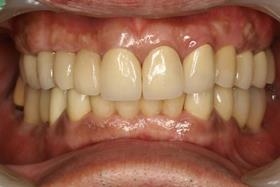

全口植牙重建

治療前VS.治療後

治療前

治療後

病患恢復自信笑容。